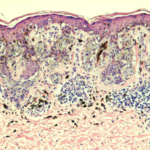

Single and aggregated atypical spindled and epithelioid melanocytes at the dermal-epidermal junction with confluence of nests. Occasional pagetoid melanocytes are noted. There is lymphohistiocytic inflammation with melanophages in the dermis. The diagnosis was rendered as a melanocytic neoplasm with usual features.

Note: The differential diagnosis is between that of a Clark's nevus with spitzoid features or a very subtle melanoma measuring approximately 0.25 mm in Breslow thickness. The margins are free of neoplasm. Former diagnosis favored.